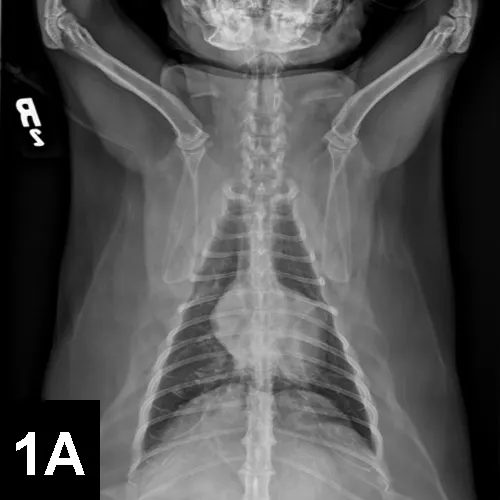

DIAGNOSTICSDual-view radiographs (see Figure 1 below) and an ECG (see Figure 2 below) were obtained at presentation.

Figure 1. Dorsoventral (A) and right lateral (B) radiographs.

• The extra heart sound on examination may have represented a diastolic gallop, as it was diastolic and of low frequency, which can indicate cardiac diastolic dysfunction. The ECG revealed sinus rhythm (heart rate, 230 beats/min) and increased R-wave amplitude (2.1 mV; normal <0.9 mV), which suggest left ventricular hypertrophy. The radiographs revealed generalized cardiomegaly, left atrial enlargement, distended and prominent pulmonary vasculature, and cardiomegaly with a patchy interstitial pattern. This combination of findings is most consistent with cardiogenic pulmonary edema.